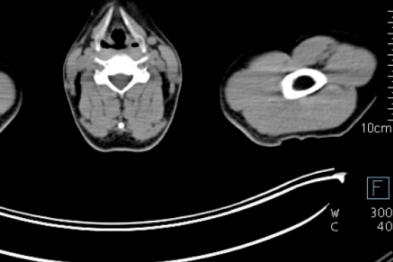

【医路有术】一间手术室搞定「诊断+治疗+评估」,毫米级精准跑赢生死时速